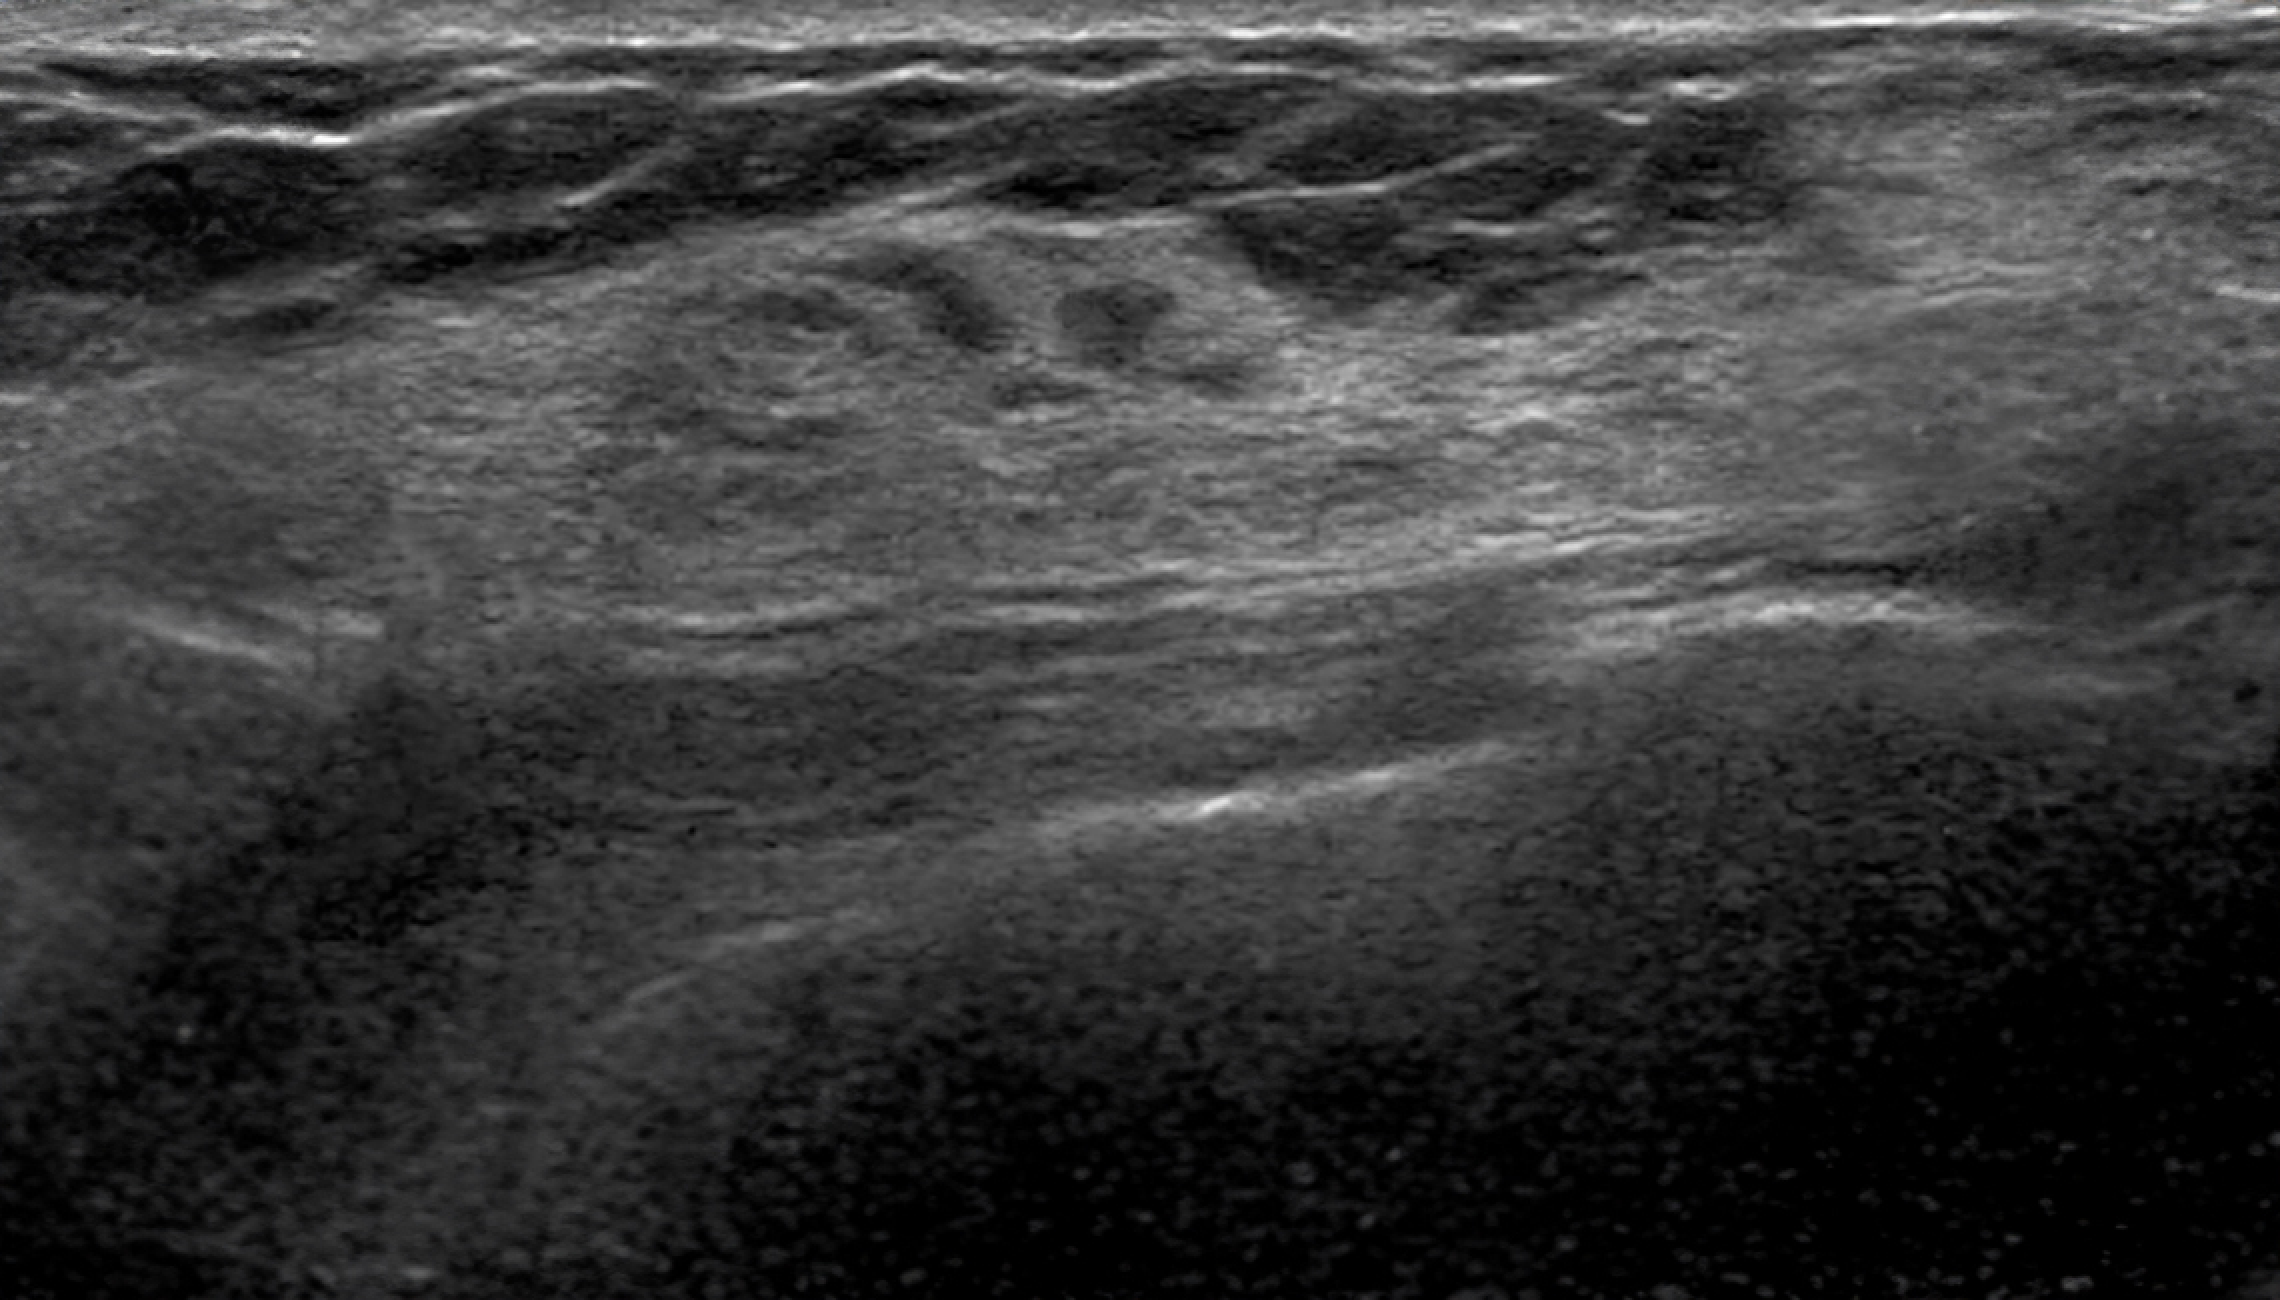

Automatic Detection of Abnormal Lesions

Automatically detects the locations of abnormal lesions in breast ultrasound images in real time.